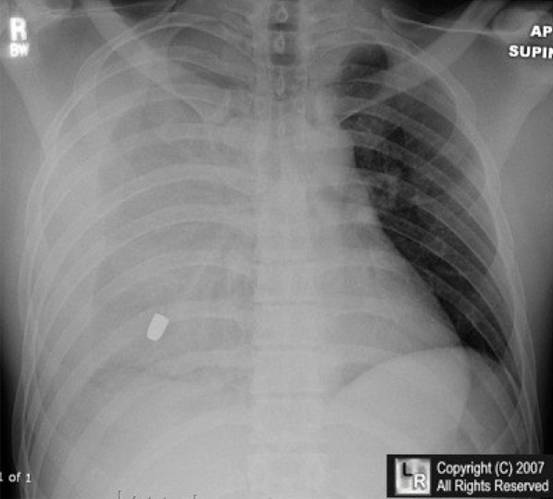

6.男性,24歲,車禍來診,訴右側(cè)胸痛,胸片如下,考慮診斷:

A. 左側(cè)氣胸

B. 右側(cè)血?dú)庑?/p>

C. 急性左心衰

D. 右側(cè)肺不張

E. 肺炎